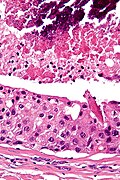

Salivary duct carcinoma. H&E stain.

LM varied arch. (sheets, nests, cords, cribriform, micropapillary), neoplastic cells line-up around cystic spaces "Roman bridges", nuclear atypia, apocrine snouts, decapitation secretions

Features - resembles ductal breast carcinoma:[1]

• Architecture: sheets, nests, cords, cribriform, micropapillary.

• Neoplastic cells line-up around cystic spaces "Roman bridges".

• Nuclear atypia (variation in size, shape, staining).

• Apocrine snouts - pseudopod-like/lollipop-like undulations of the cell membrane.

• Decapitation secretions - apocrine snouts (membrane bound blobs of cytoplasm) that have separated from its mother cell.

• Similar to ductal breast carcinoma - key to remember.

Salivary duct carcinoma. 59 y man with a 3 cm right superficial parotid mass. A. Low power shows a predominance of patterns similar to in situ, micropapillary (white arrow), Roman bridge (green arrow), cribriform (blue arrow) patterns. B. Careful search reveals occasional invasive bars (arrow). C. The bar comprises the usual invasive pattern of adenocarcinoma, with cancerous cell clusters, isolated glands, incomplete glands, and adjoined/fused glands. Note the lighter color of stromal desmoplasia (arrows). D. The in situ component has more uniform nuclei than the invasive component. Note the comedo necrosis. E. Cancer cells expressed CK7. F. Cancer cell nuclei were positive for androgen receptor. Not shown: tumor was negative for SOX10 and P63.